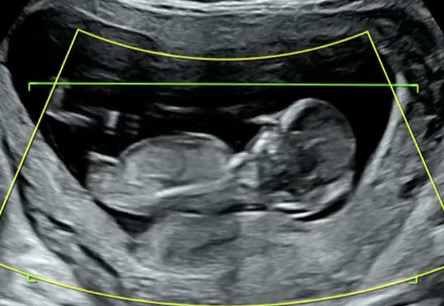

12주차! 각도법 봐주실수있나여..?

오늘 보고왓는데 다리꼬고 잇어서 잘 안보이더라구여 ㅠㅠ 혹시 이사진으로도 볼수있을까영 궁금해유..